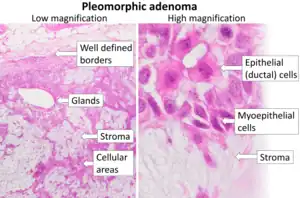

| Cytopathology of pleomorphic adenoma (Pap stain). It can usually be diagnosed by its typical fibrillary stroma (mesenchyme). Stromal cell nuclei are small. Myoepithelial cells are usually the predominant cell type, and their nuclei can have various shapes but are usually more elongated than in epithelial cells. Epithelial cell nuclei may have prominent nucleoli.[2] | |

Pleomorphic adenoma (or benign mixed tumor) is a common benign salivary gland neoplasm characterised by neoplastic proliferation of epithelial (ductal) cells along with myoepithelial components, having a malignant potentiality. It is the most common type of salivary gland tumor and the most common tumor of the parotid gland. It derives its name from the architectural Pleomorphism (variable appearance) seen by light microscopy. It is also known as "Mixed tumor, salivary gland type", which refers to its dual origin from epithelial and myoepithelial elements as opposed to its pleomorphic appearance.

Histology

Morphological diversity is the most characteristic feature of this neoplasm. Histologically, it is highly variable in appearance, even within individual tumors. Classically it is biphasic and is characterized by an admixture of polygonal epithelial and spindle-shaped myoepithelial elements in a variable background stroma that may be mucoid, myxoid, cartilaginous or hyaline. Epithelial elements may be arranged in duct-like structures, sheets, clumps and/or interlacing strands and consist of polygonal, spindle or stellate-shaped cells (hence pleiomorphism). Areas of squamous metaplasia and epithelial pearls may be present. The tumor is not enveloped, but it is surrounded by a fibrous pseudocapsule of varying thickness. The tumor extends through normal glandular parenchyma in the form of finger-like pseudopodia, but this is not a sign of malignant transformation.